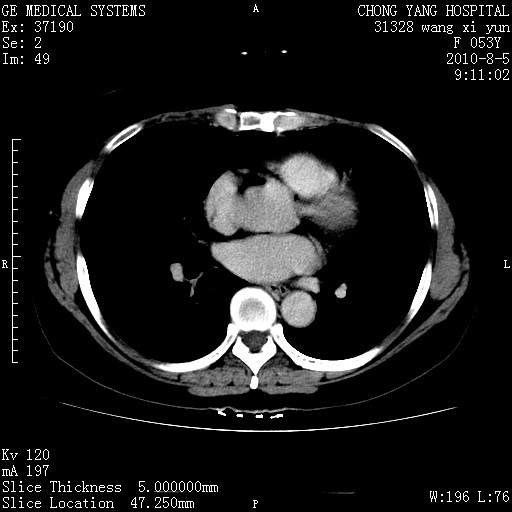

标题: CT28214:F41Y 血尿二十天,建议盆腔平扫加增强。

胆管细胞ca?

1)考虑肝左叶胆管细胞癌。2)脂肪肝。

支持胆管细胞ca。